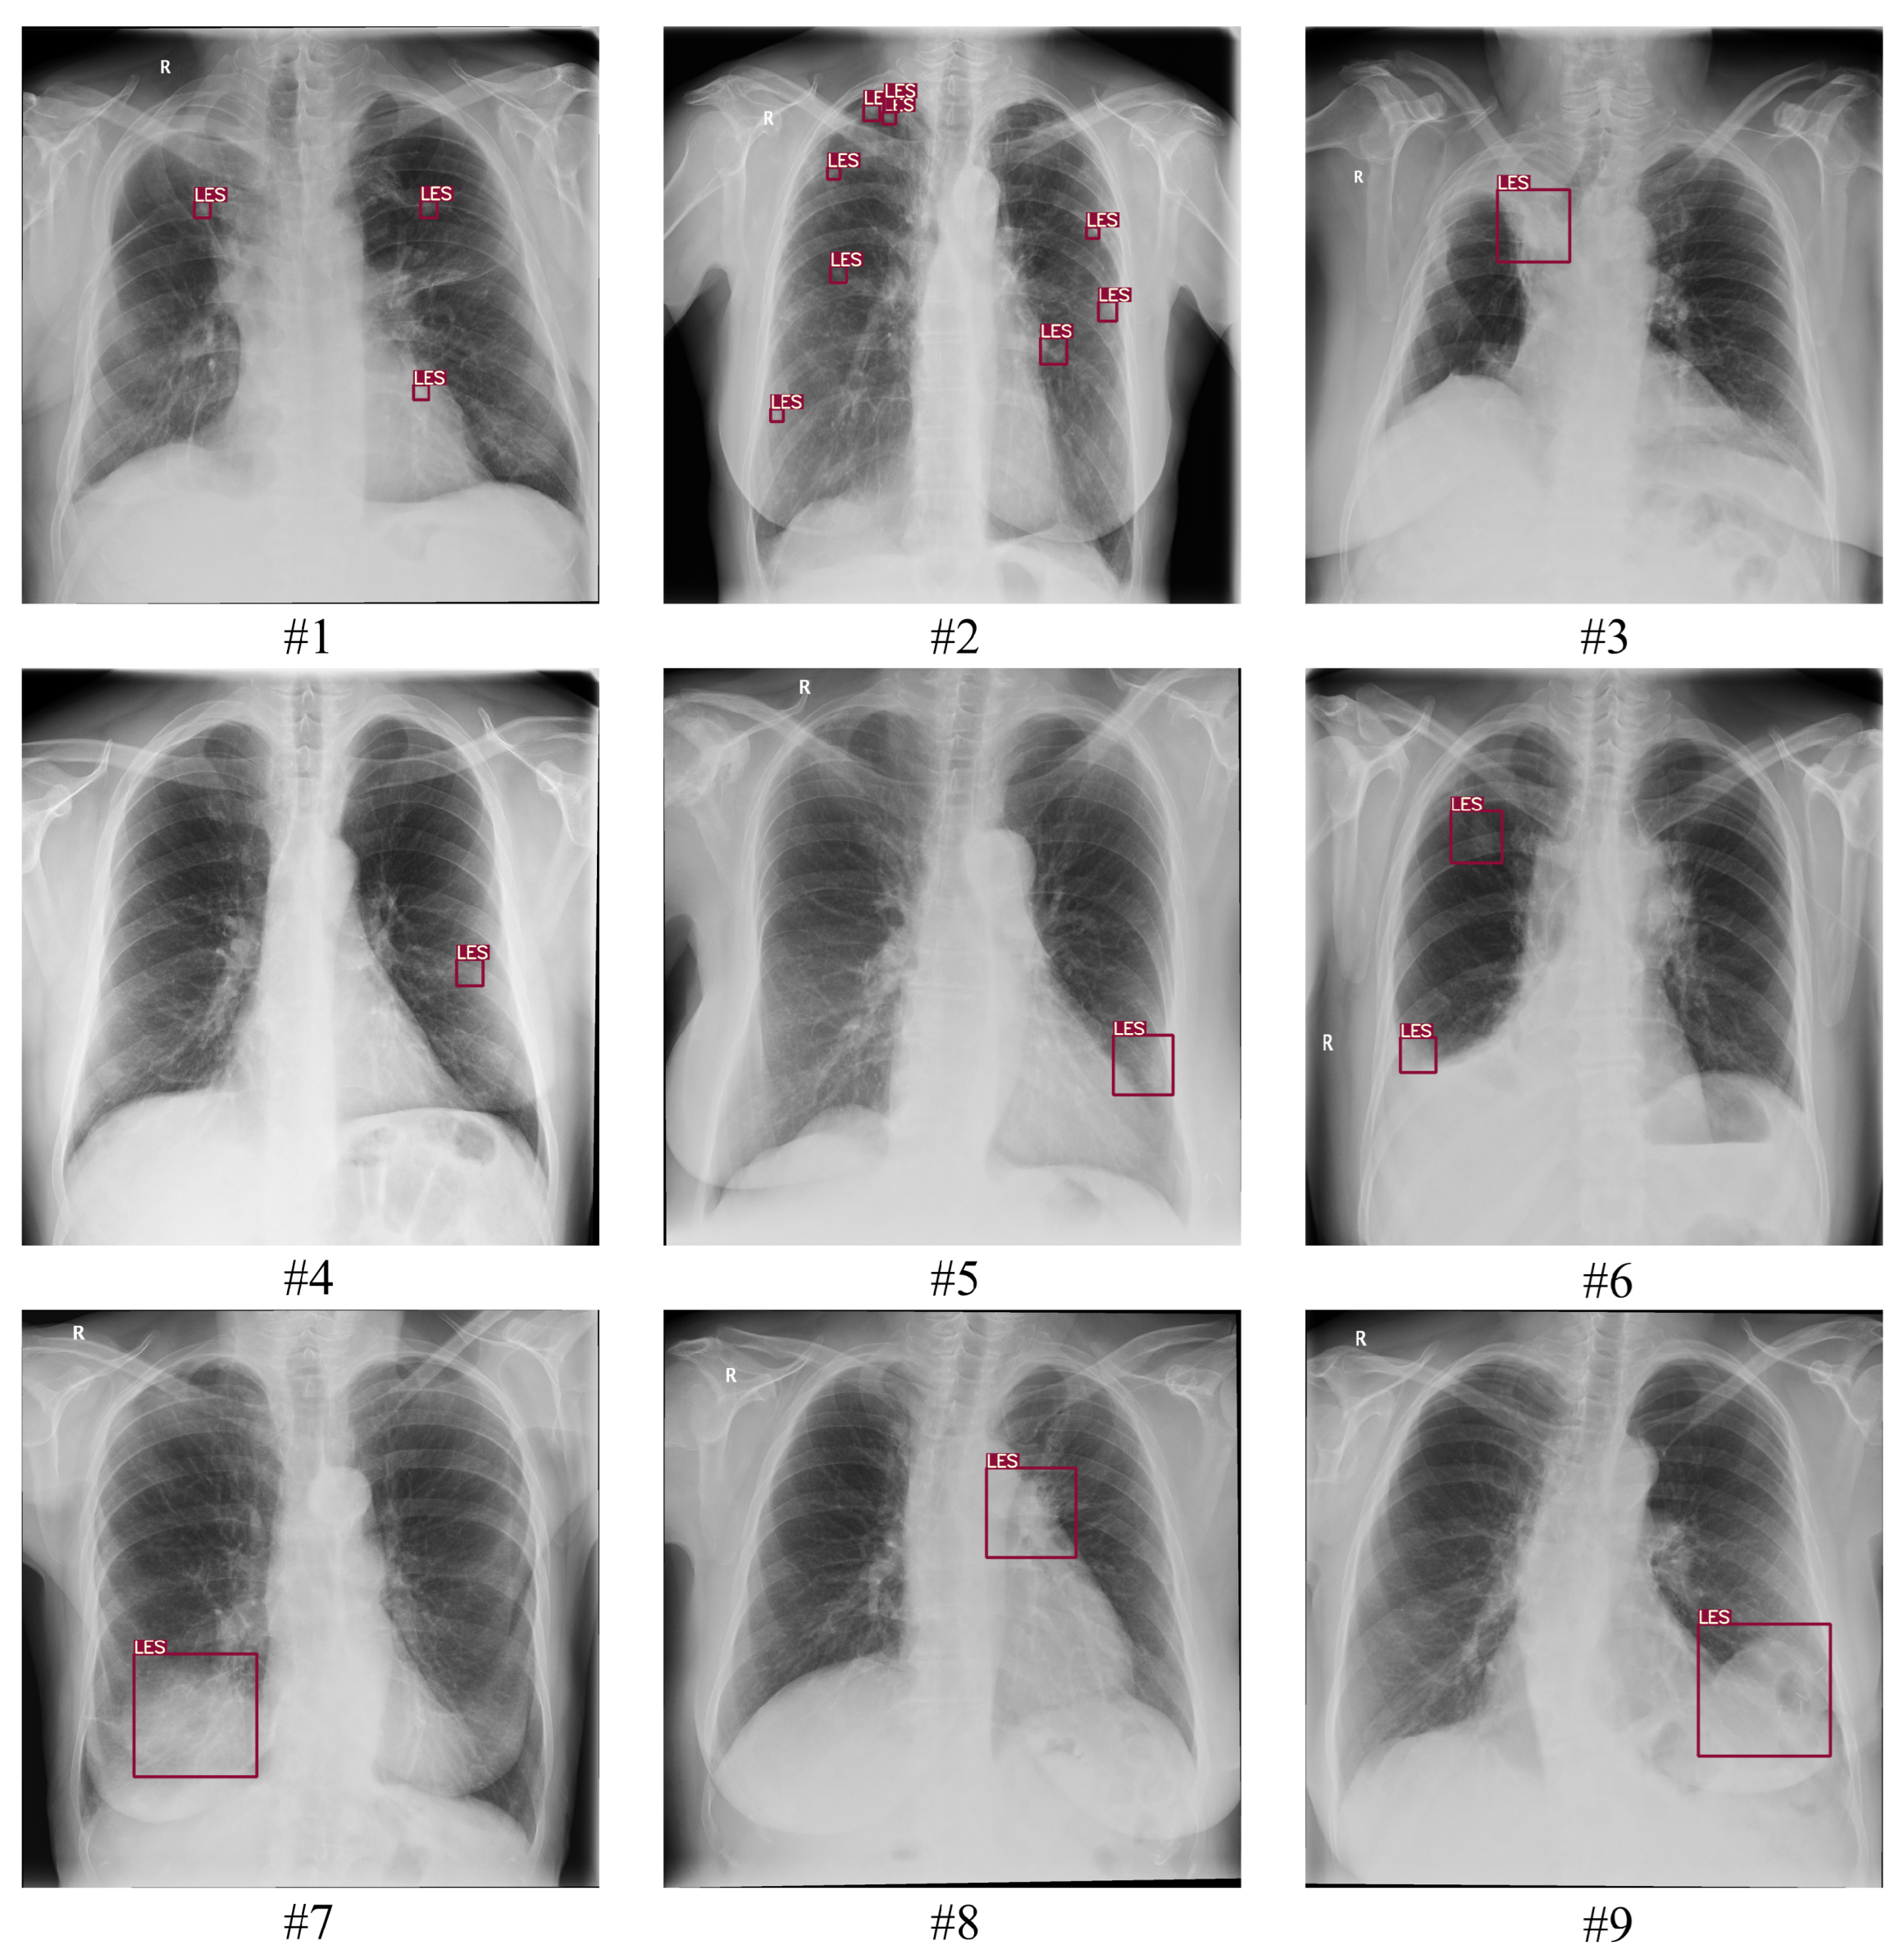

3.3. Ground Truth

3.4. Assessment